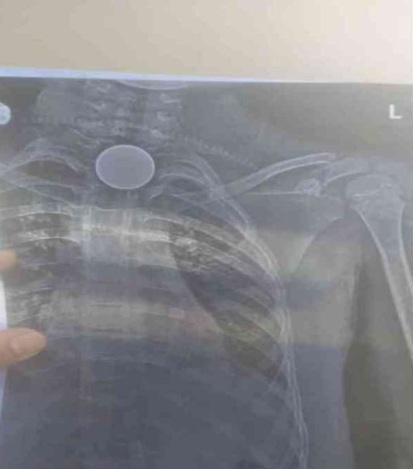

कोरबा: 1 नवंबर 2025 छत्तीसगढ़ के कोरबा जिले में 8 साल की बच्चा सिक्का निगल गया, जिससे उसकी मौत हो गई. मृतक मासूम शिवम सारथी केजी 2 का छात्र था. जानकारी के मुताबिक, धरमजयगढ़, जिला रायगढ़ निवासी 8 वर्षीय शिवम सारथी अपने पिता मदन सारथी के साथ कोरबा के गोढ़ी गांव में रुके हुआ था. इस दौरान शिवम सिक्का निगल गया. गले में सिक्का फंसने के बाद परिजन उसे लेकर जिला मेडिकल कॉलेज अस्पताल पहुंचे, जहां उसका इलाज नहीं हो सका जिसके बाद परिजन उसे लेकर निजी अस्पताल जाने लगे जहां रास्ते में उसकी मौत हो गई,पुलिस ने परिजनों के बयान दर्ज कर आगे की करवाई शुरू कर दी है।